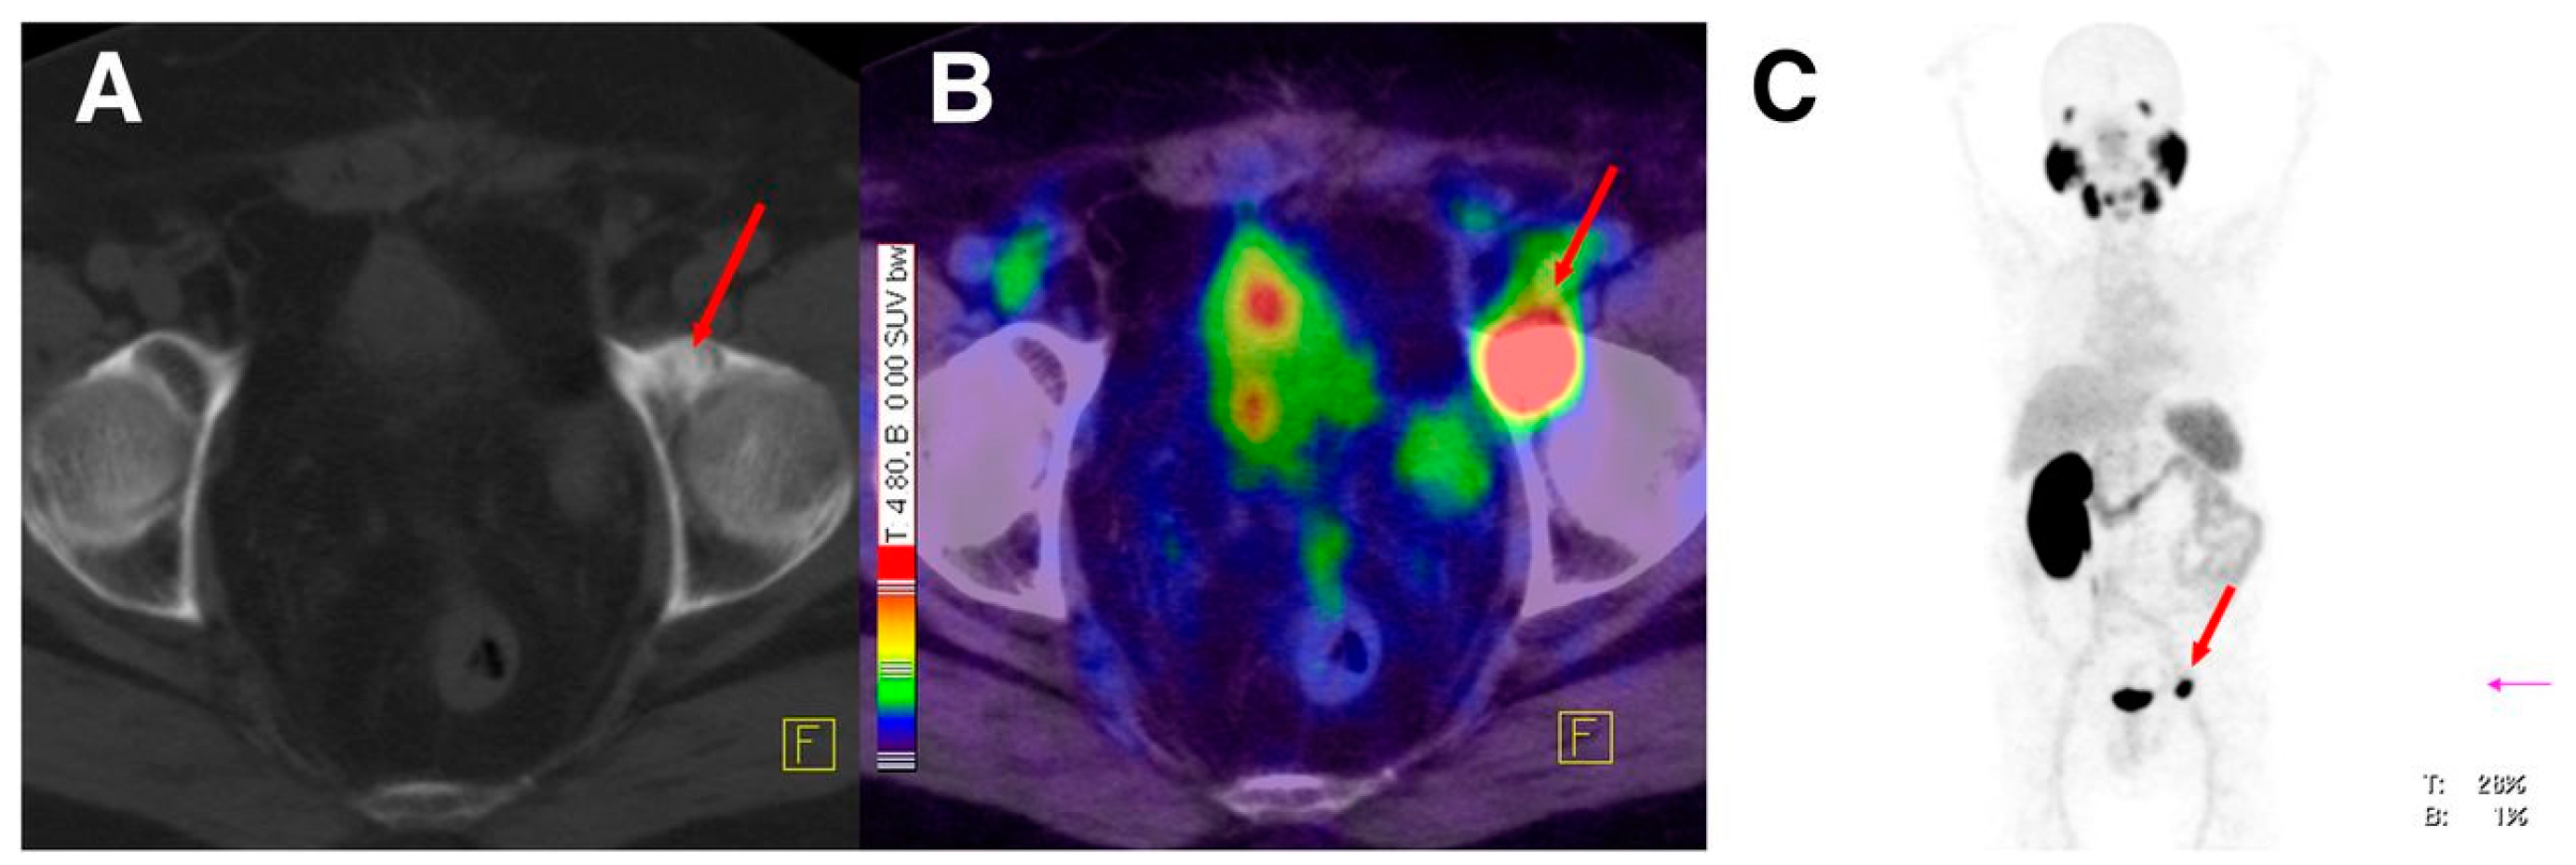

The PSMA inhibitor PSMA-617 labeled with 68Ga was also clinically assessed in the diagnosis of prostate cancer by PET-CT [146]. 68Ga-PSMA-617 shows lesions of prostate cancer with high contrast, especially in late images (Figure 20). Maximum contrast of tumor lesions was achieved between 3 and 4 h after injection.

Figure 20.

(A–C) 68Ga-PSMA-617 PET/CT of a patient at 1 h after injection. Red arrows point to a bone metastasis with SUVmax of 21.7 at 1 h and 32.6 at 3 h after injection. (A) Low dose CT; (B) Fusion of PET and CT; (C) MIP of PET/CT. MIP = maximum-intensity projection (Reprinted with permission of [146]).